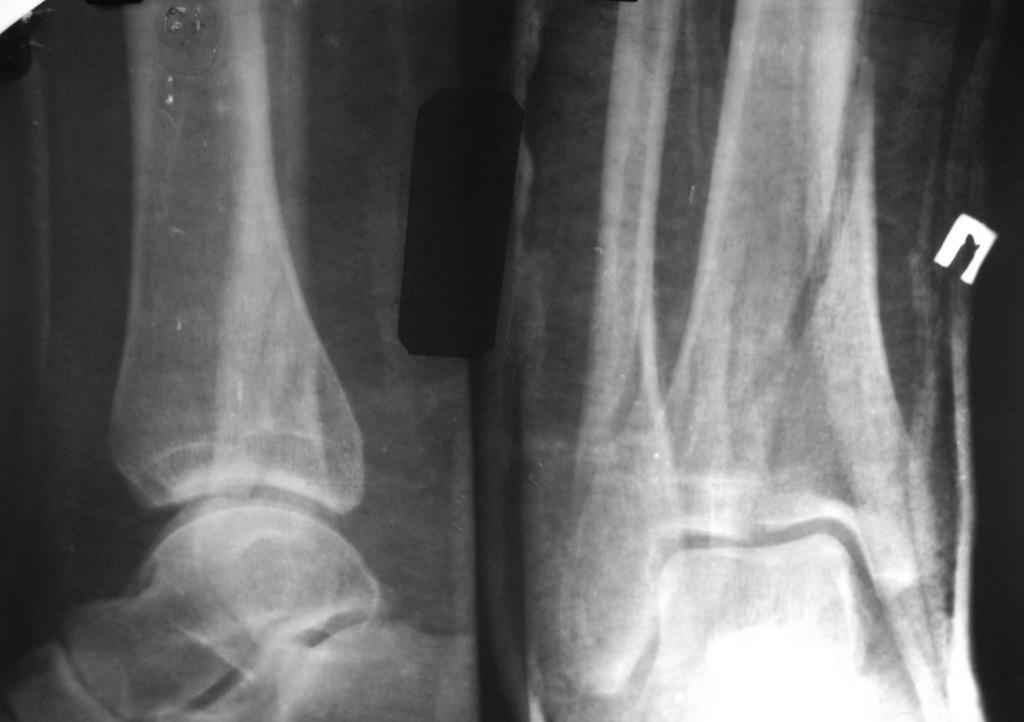

[Ortho] перелом пилона. тактика лечения

прошу прощения за то, что забыл приложить снимки

Имя     : IMG_3040_12.jpg